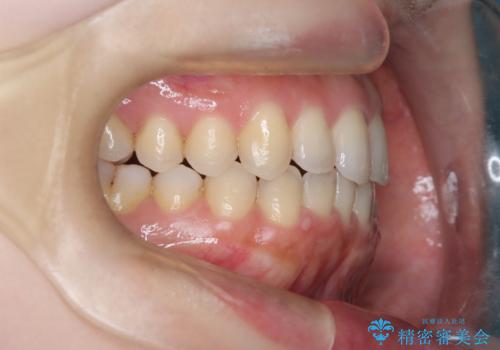

【オープンバイト】前歯のがたがたをなおしたい。

- 笑った時の前歯の見た目が気になることを主訴に来院されました。

上の歯が下の前歯を少し隠すぐらいを目指し、インビザラインにて治療を行いました。